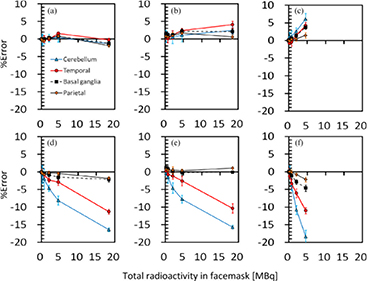

Figure 3 also shows results from the 3D brain phantom experiments, which demonstrate the magnitude of errors in the regional radioactivity assessment for the given ROIs as a function of radioactivity in the face mask for each of cases 2‒4, shown in figure 1. When the radioactivity was supplied only to the face mask (case 2), the difference from the brain phantom alone (case 1) was less than +/ − 2% in all regions, when the outside-FOV scatter correction procedures were excluded. However, when the outside-FOV scatter compensation procedures were included, errors were increased in all regions and reached −10% and −15% in the temporal lobe and cerebellum regions, respectively. For case 3, in which additional radioactivity was placed in the lung area, which corresponded to the maximum dose during inhalation of 15O2 in a clinical study, errors were slightly increased to 3% at 10 MBq of gaseous radioactivity in the face mask, when the outside-FOV scatter compensation was excluded. Inclusion of the outside-FOV scatter correction increased the errors to a similar level to those in case 2, but they were consistently worse than those without the outside-FOV scatter correction. When part of the face mask was placed outside FOV, errors were 2‒6%, and −2‒19% at the radioactivity of 5 MBq inside the face mask, corresponding to the exclusion and inclusion of the outside-FOV scatter correction, respectively.

Figure 3. Errors in the regional radioactivity concentration for the 4 ROIs selected on the reconstructed PET images as a function of radioactivity in the face mask for three different configurations of case 2 (a, d), case 3 (b, e) and case 4 (c, f) shown in figure 1. All data was corrected for the scatter by means of the single-scatter simulation method, with and without the inclusion of the outside FOV scatter, corresponding to (a, b, c) and (d, e, f), respectively. Blue solid, red solid, black dashed and black solid lines correspond to the cerebellum, temporal lobe, Basal ganglia and Parietal regions, respectively.

Standard image High-resolution imageFigure 4 shows counting-rate characteristics observed in the 3D brain-phantom experiment for each of cases 2, 3 and 4, namely the prompt, true + scatter and random events in the left column, as well as NECR in the right column, as a function of radioactivity inside the face mask. For the case 2 experiment, true rates increased when radioactivity in the face mask was increased almost linearly, as the random rates were small. NECR also increased almost linearly as the face-mask radioactivity was increased. In case 3, on the other hand, random rates were considerably increased compared with case 2. The random rates were even higher than the true + random rates, with the total radioactivity in the face mask being greater than 5 MBq. NECR in case 3 (figure 4(d)) tended to be saturated at the face mask radioactivity >5 MBq, and smaller than in case 1 (figure 4(b)). In case 4, the experiment was carried out only for a range of the face-mask radioactivity <5 MBq. The NECR shown in figure 4(f) reflect smaller values than in case 2 at the total radioactivity in the facemask <5 MBq.

Figure 4. Counting-rate characteristics as a function of radioactivity in the face mask observed in the 3D brain-phantom experiments for three different configurations of case 2 (a, d), case 3 (b, e) and case 4 (c, f), shown in figure 1. Figures a, c and e represent prompt, true + scatter, and random count rates for the three configurations and figure b, d, and f represent NECR.